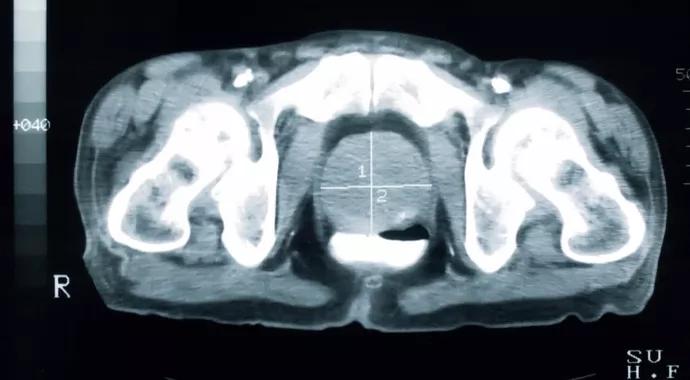

During the past decade, two technologies have emerged that may change the future of external beam radiation therapy for prostate cancer – stereotactic body radiation therapy (SBRT) and proton beam therapy (PBT).

SBRT and PBT are forms of external beam radiation that have theoretical advantages over IMRT.

PBT is a technology that has been used to treat prostate cancer since 1976. Protons are heavy charged particles with a very different radiation dose distribution compared with X-ray photon-based therapy.

Unique to PBT is the Bragg peak, which is the deposition of a burst of energy at the tail end of a proton’s range. This physical property allows for the relative sparing of the radiation dose to normal tissues beyond the Bragg peak, potentially reducing the toxicities to those organs.